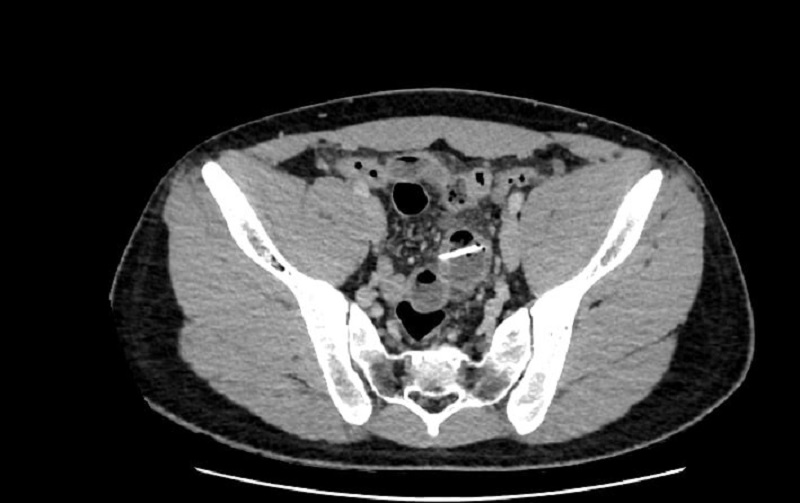

Bệnh nhân chụp CT phát hiện dị vật cản quang đoạn cuối hồi tràng

Dù siêu âm và X-quang ban đầu chưa phát hiện bất thường, nhưng kết quả chụp cắt lớp vi tính (CT-scanner) thấy dị vật cản quang đoạn ruột hồi tràng (đoạn cuối của ruột non) vùng tiểu khung đâm xuyên qua lớp cơ và thanh mạc (lớp ngoài cùng), thâm nhiễm xung quanh.